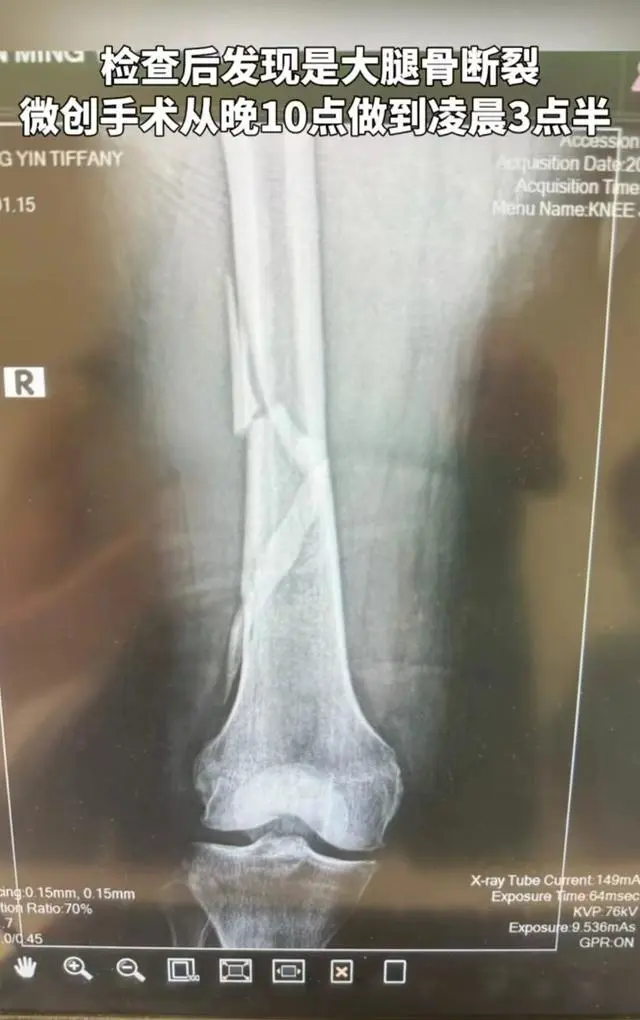

向太陈岚虽然不是娱乐圈明星,却比明星还要火,特殊是2022年开启直播带货后,她的热度有增不减,从营销美貌到营销好婆婆,完尤物设爆棚。 4月26日,许久没有更新短视频的向太突然更新,称本身在浴室沐浴的时间不鉴戒跌倒,导致大腿骨断裂,经历了5个小时的手术。 从视频中可以看出,向太全身包裹得严严实实的,躺在担架上,医护人员将她小心翼翼地推出来,老公向华强全程陪伴,脸上写满了担心。 向太过后表现,怕救护车开到家里引起附近人的推测和猜疑,为了不占用公共资源,本身在浴室硬躺了一个晚上,没有叫救护车,直到第二天早上才喊了私人医生。 通过专业查抄,向太确诊大腿骨断裂,整个过程没有掉一滴眼泪,现在大腿里尚有一根很长的钛金属管和四根髓钉。 向太挖苦本身是名副实在的“钢铁女侠”,并表现这点小妨害无所谓,要大胆笑对妨害,笑对人生。 对于家人来说,向太的不测让人猝不及防,除了向华强,儿媳妇郭碧婷更是倍加担心,前段时间好不轻易颠末头脑斗争,临时丢下孩子加入了《浪姐》,逐日高强度的练习已经让她喘不外气来,现在婆婆又发交易外,更是压力大增。 5月3日,向太发视频回应了她和郭碧婷融洽的婆媳关系,她透露郭碧婷得知婆婆腿伤的消息后,立马带着一双儿女来看望她。 孙女小奶皇看到轮椅上的奶奶,非常懂事乖巧,非常暖心地说奶奶受伤的那条腿很痛,以后要坐那条不受伤的腿上面。 除此之外,小奶皇还会给奶奶挑选衣服,当天向太身上这身仙气飘飘的衣服就是孙女切身挑选的,小小年龄就很有审雅观。 除了衣服仙气外,向太还专门搭配了一顶白色的帽子,再看手上的大钻戒,犹如一朵蒲公英,大得有点不真实,耳环手链和项链装饰了一身,尽显壕气优雅。 有人质疑向太抱病,很可能郭碧婷会因此退赛,向太回应了此事,并喊话郭碧婷千万不要这么做,因为当初加入这个节目夷由了很久,直到末了一刻才允许下来,不会轻易放弃。 向太还大赞郭碧婷唱歌好,在节目里宛如一股清流,并坚信儿媳能走到末了。 婚后,郭碧婷的重心都在老公孩子身上,身材也日渐发福,网友常吐槽她不自律,现在加入节目,向太曝郭碧婷很享受这个工作过程,没有孩子的束缚,可以享受难过的沉寂。 向太还表现郭碧婷最大的劳绩是瘦了,腰细了,整个人也薄了,乃至双下巴也不见了。 从向太的语气可以听出,她对郭碧婷满是喜欢和欣赏,两人不仅长得像,而且还全是台湾人,冥冥中就注定有特殊的缘分。 更紧张的是郭碧婷是向太切身挑选的儿媳妇,以是才会越看越中意。向太也表现本身没有白疼郭碧婷,两人之间的关心和爱护都是相互的,也盼望郭碧婷享受乘风的录制过程,多交点朋侪,赢了最好,输了也赚到了履历。 这样的婆媳关系,你羡慕吗? |